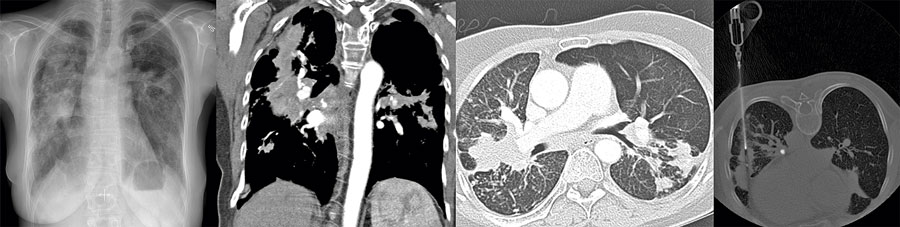

Sotrökslunga är en ny sjukdom i Sverige

Fallbeskrivning

Exponering för rök från biomassa är orsaken